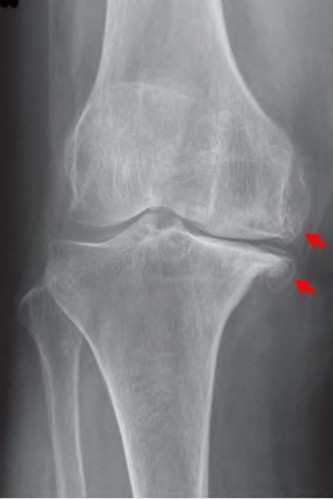

The radiograph seen in Figure A reveals varus alignment of the knee, with medial tibial deficiency; from this X-ray the patient appears to have unicompartmental arthritis. Treatment options for unicompartmental arthritis include high tibial osteotomy, interpositional arthroplasty, unicondylar knee replacement and total knee replacement. Interpositional arthroplasty became popular in the 1950’s when early outcomes analysis seemed to indicate good results; long term follow up in one study found 0/12 excellent results, with all patients requiring conversion to TKA. This procedure is no longer recommended due to the poor long term outcomes.

While an osteotomy is still used for young and active patients, unicompartmental or total knee arthroplasty have largely replaced this treatment in older patients. Advantages of UKA and TKA include more predictable relief of pain, quicker recovery, and better long-term results. Criteria for UKA include limited unicompartmental disease, no more than a fixed 10 degrees of varus or 5 degrees of valgus deformity from neutral and an intact anterior cruciate ligament with no signs of medial lateral subluxation of the femur on the tibia; this patient is therefore not a good candidate for this procedure.

Total knee arthroplasty can be used to provide predictable pain relief in a patient with unicompartmental and tricompartmental degenerative disease and varus malformation of the knee and for this patient is the best option.

A 67 year-old woman sustained an ACL tear while playing basketball when she was 35 years-old. She has noted progressive leg deformity and episodes of giving way, and now has pain preventing activity. Non-operative management has failed to provide relief. Treatment should consist of?